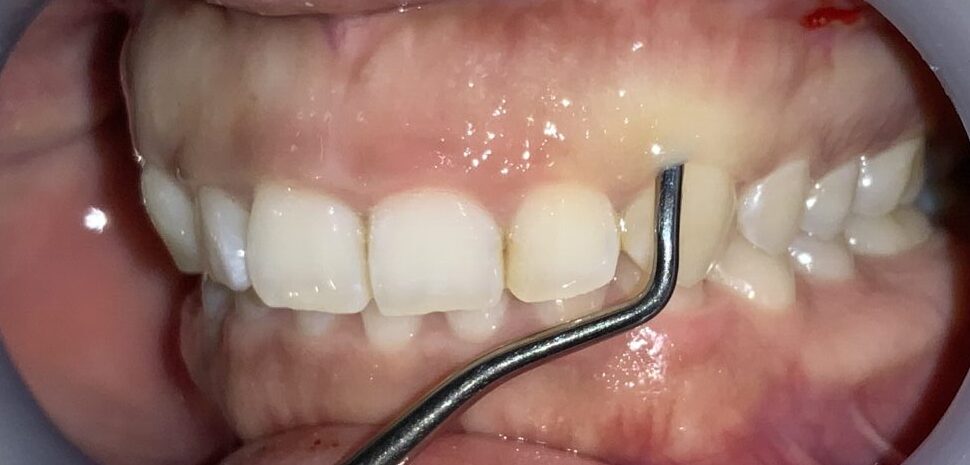

犬歯です。

歯ぐきの部分が大きいですね。しかも歯ぐきが薄いので、検査器具が歯ぐきの下から透けています。

最後に4番目の歯です。

1本1本、歯ぐきの被り方や厚みは違いますから、その点を見極める診察が大切です。